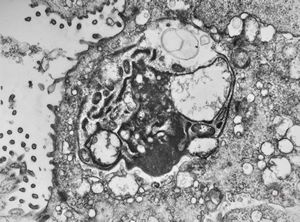

M,82y. | Helicobacter pylori - antrum pylori